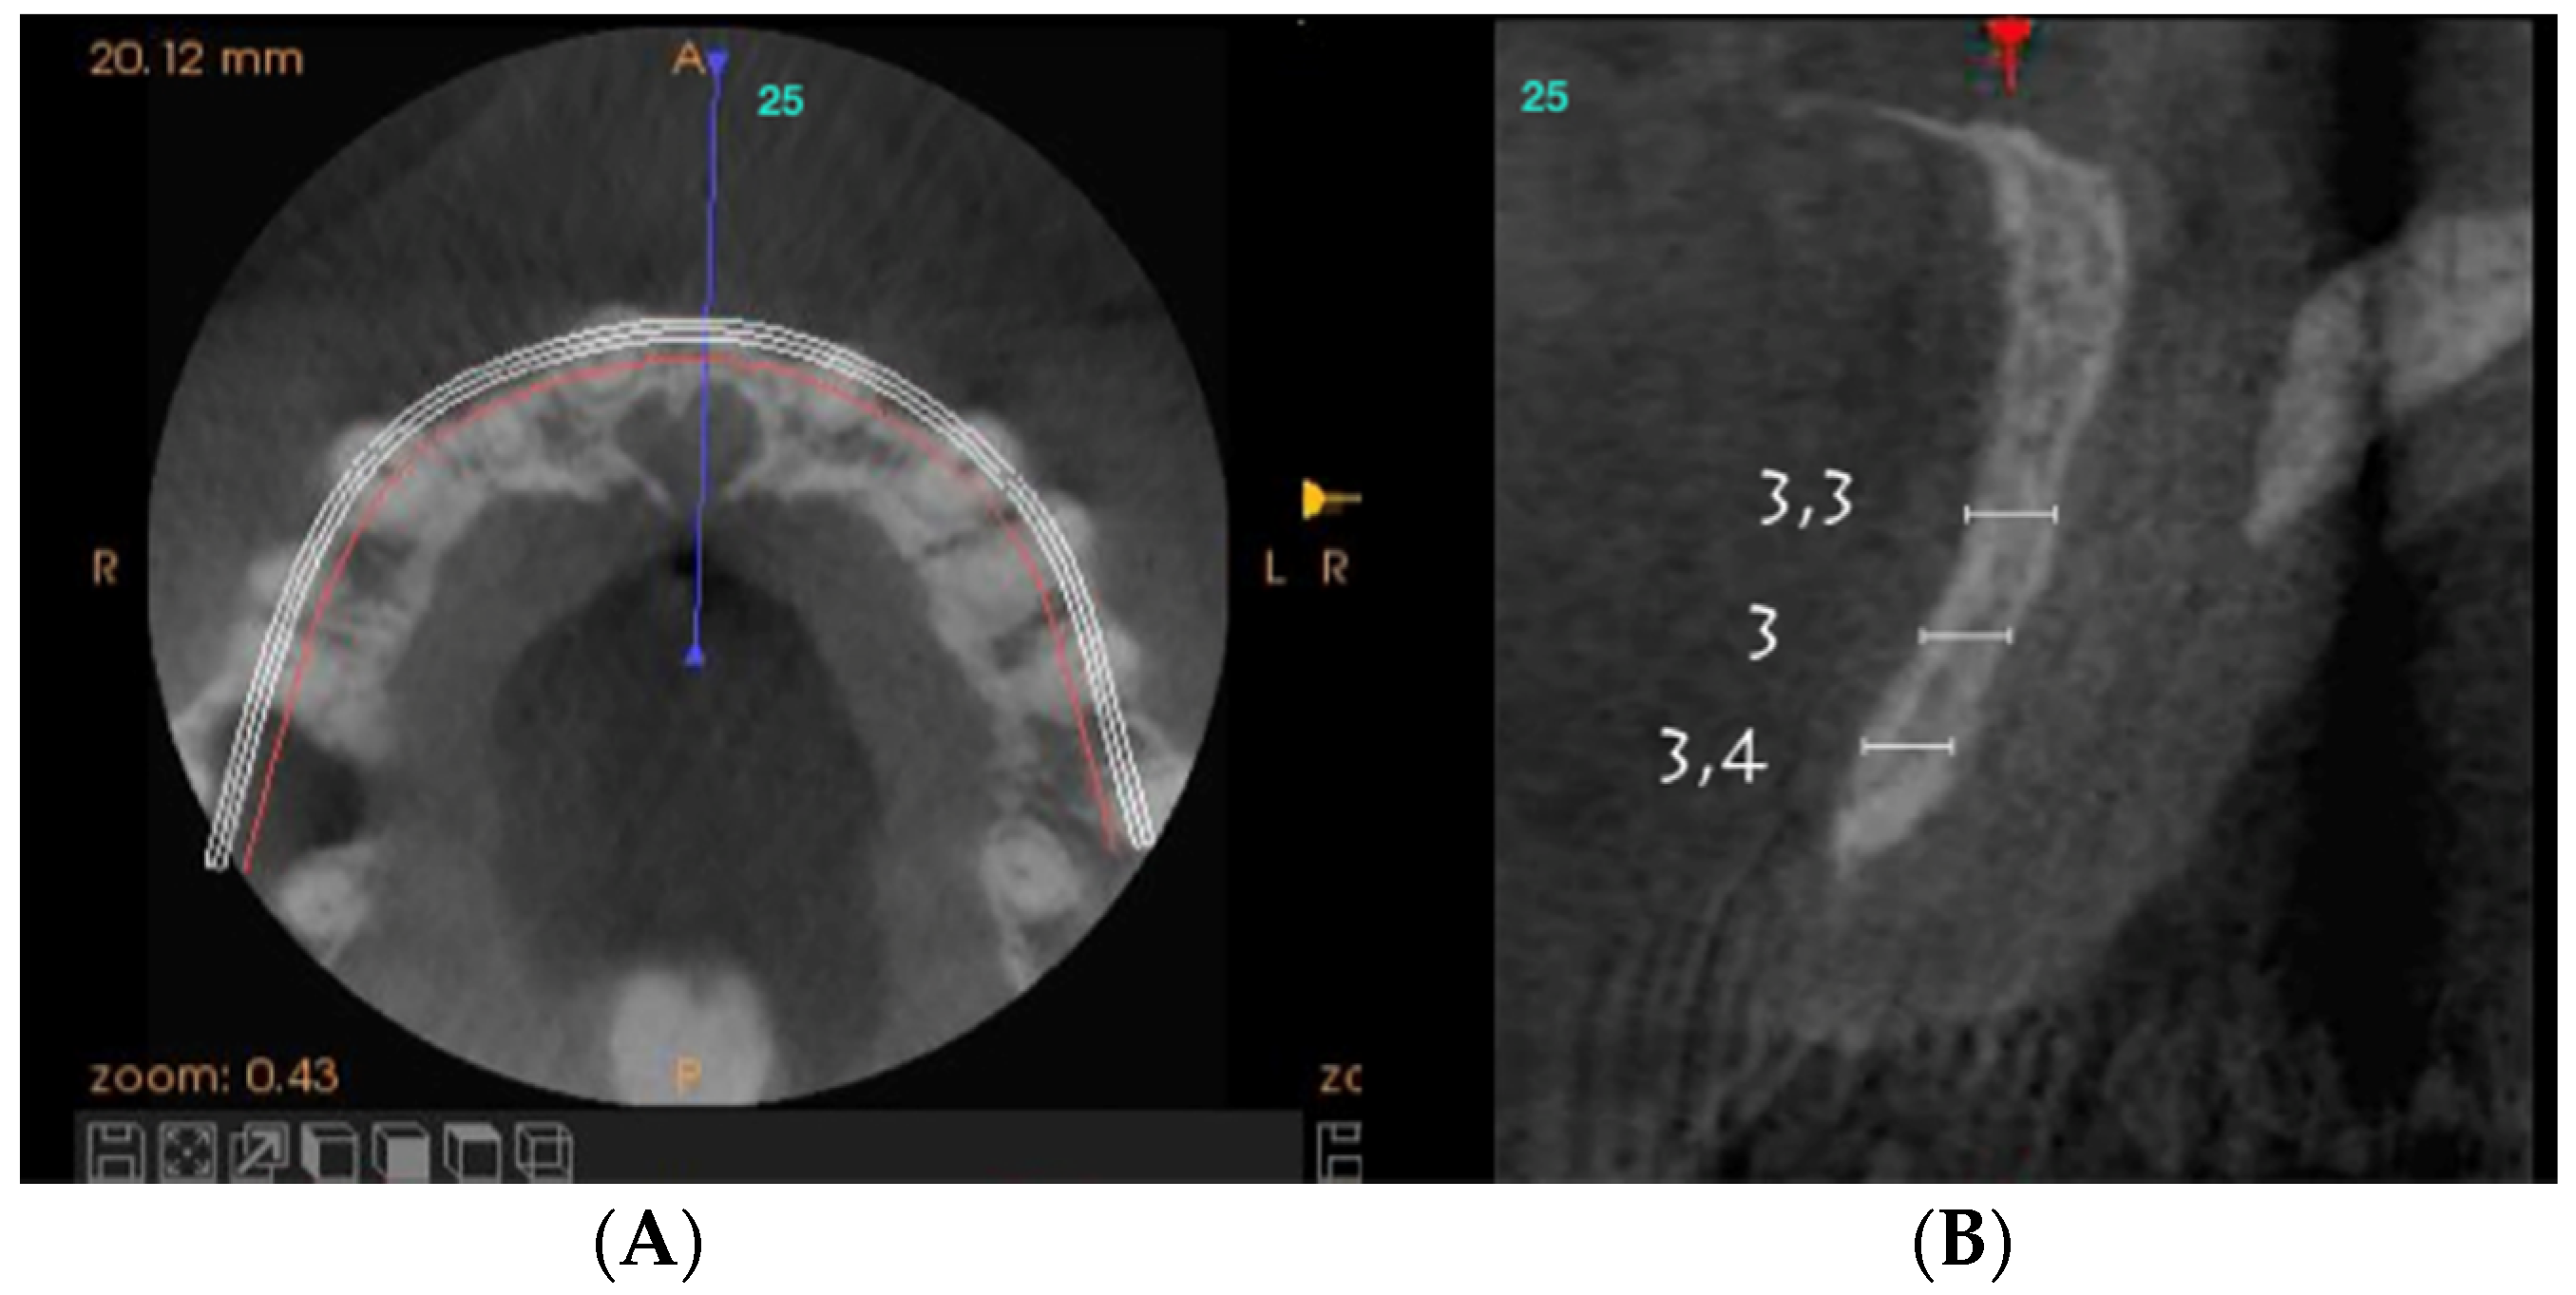

Axial sections corresponding to the middle part of the NPC showed the collapse of the vestibular plate and revealed the conduit’s size. All the cases presented thinning of the palatal ridge due to marked widening of the incisive foramen (Figure 2); so, according to the SAC Classification (i.e., simple, advanced, or complex), they were categorized as complex [2]. In addition, careful consideration had to be given to the nasopalatine bundle for correct three-dimensional positioning of the implant. Since the vertical and horizontal defects demanded bone augmentation before implant placement [17], a diagnostic wax-up was performed to determine the amount of bone needed in each case.

Figure 2.

Representative sections of a Cone Beam Computed Tomography (CBCT) scan in which the bone thickness of the maxillofacial region and the widening of the incisive foramen are observed. (A) Occlusal view. (B) Sagittal view.

2.4.1. Bone Ridge Thickness

For each patient, pre- and post-treatment CBCT measurements of the anterior ridge thickness of the aforementioned foramen were taken at different heights, i.e., 4, 8, and 14 mm apical to the marginal bone ridge. CBTC was performed at 90 Kv and 10 mA, with an 18-second exposure cycle on a Promax-3D plus equipment (Planmeca, Finland). The obtained images were analyzed with Romexis 4.4.0.R. A field of view of 40 mm by 50 mm was used, with an isoropic voxel size of 75 µm (0.075 mm). Serial slices (0.5 mm in thickness) with 0.5 mm reconstruction intervals were analyzed.

For the scanning procedure, the occlusal planes were oriented parallel to the horizontal plane. Medical imaging recording protocols were used for comparative measurements. First, image relationships were determined following the process of superimposition of tomographic images obtained by CBCT by using the Canny edge detection module of MATLAB R2018a (64-bit). Overlays were made in the areas of interest, obtaining identical reference points as those provided by the Canny filter.

For each patient, pre-surgical measurements were taken in the vestibular table observed from the sagittal plane, from the vestibular cortex to the anterior cortical wall of the NPC. In the same fashion, the vestibulo–palatine width was measured between 6.5 and 9.5 months (7 months on average) after implant activation.

Pre-surgical vestibulo–palatine width (mean ± standard deviation) of the anterior ridge at different heights (4, 8, and 14 mm apical to the marginal bone ridge) was 3.5 ± 2.0 mm; 5.4 ± 1.5 mm, and 6.1 ± 1.9 mm, respectively. Post-treatment total vestibulo–palatine width was 10.1 ± 2.0 mm, 10.5 ± 1 mm, and 13.4 ± 3.0 mm, respectively (Table 4).